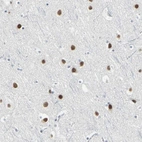

Immunohistochemical staining of human cerebral cortex shows strong nuclear positivity in neurons.